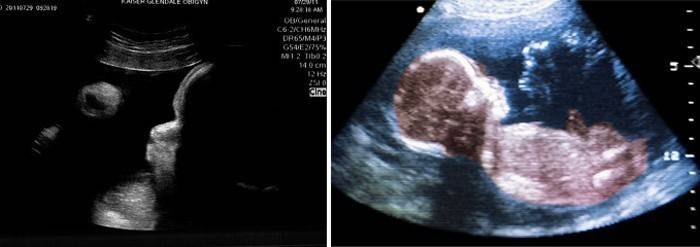

Examen de ultrasonido (Uzi)

En la semana 39, es posible que se necesite un ultrasonido solo para aclarar los matices y determinar las tácticas de manejo del trabajo de parto, también lo prescribe un médico. El médico determina la duración del embarazo por ultrasonido, el peso y la altura estimados del feto, todos sus órganos y tejidos, el grado de madurez y desarrollo, y también ve otros indicadores de ultrasonido. Es importante evaluar la condición del útero y su tamaño, la madurez del cuello uterino y su preparación, la cantidad de líquido amniótico y su condición. Se determina el grado de madurez de la placenta: la norma para este período es el tercer grado de madurez, y cuanto mayor es el grado, más antigua es la placenta peor que su función. También es importante evaluar tanto la ubicación como la longitud del cordón umbilical; si está ubicado en el cuello del feto, esto requerirá atención especial.